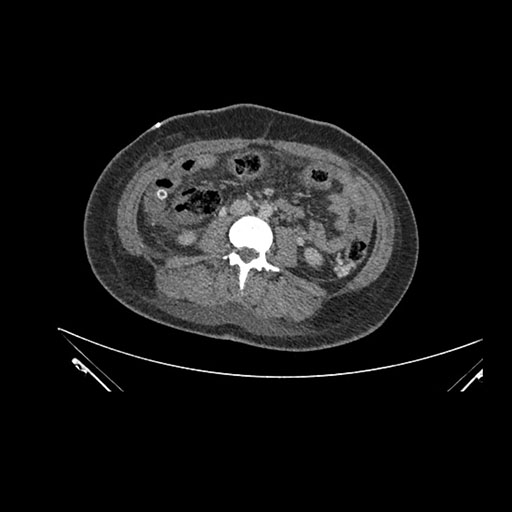

Imaging Analysis

Look through the patient's CT scan to identify any areas of concern for the necessary procedure.

Coronal Arterial

Coronal Venous

Based on initial findings, which issue(s) would you be most concerned about?